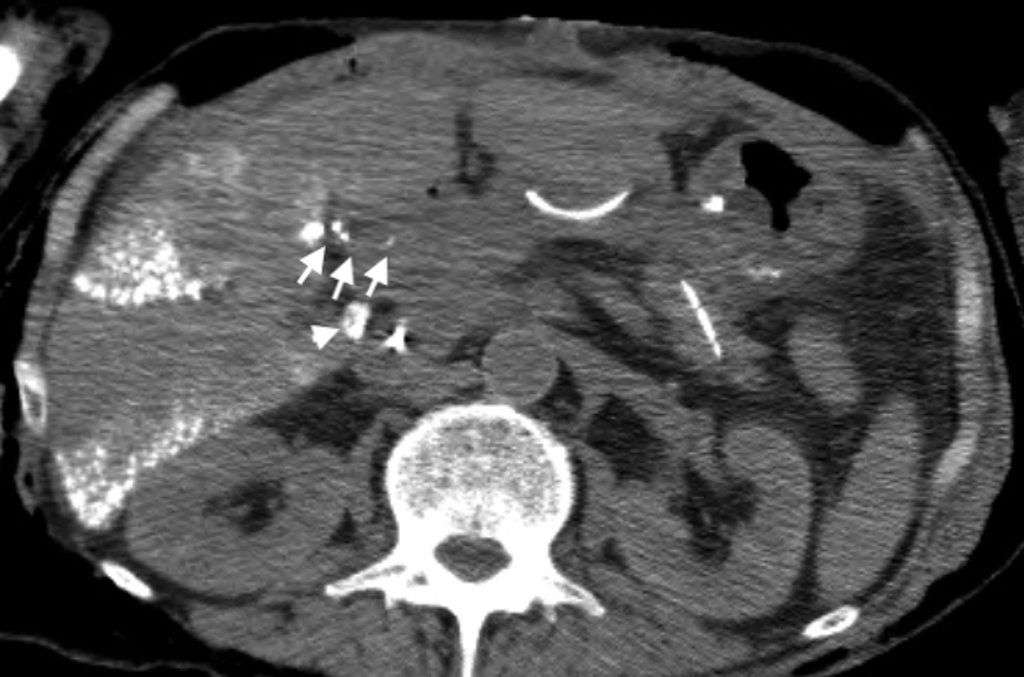

CT taken the next day after PTL demonstrates fine and tortuous lymphatics containing lipiodol at the hepatoduodenal ligament (arrows). The tip of the drainage tube was seen just behind the hepatoduodenal ligament (arrowhead).

本報告例ではPTL後もリンパ漏が持続したため,OK432の腹腔内投与も併用した.OK-432の作用機序は局所の炎症をじゃっ起することによりリンパ管を閉塞することと考えられている13).上記のようにOK-432によるリンパ漏の治療は乳糜胸の治療が多く報告されており,腹腔内投与はスペースが広いため薬剤が薄まり治療効果が低いと考えられていた7).しかし,リンパ漏出部位にカテーテルを誘導し,そこに選択的に投与を行い奏効したとする報告がある13).我々の報告例はドレーンの先端が肝十二指腸間膜の背側にあり(Fig. 4,arrowhead),まさにリンパ漏出部位のすぐ近くにOK-432を選択的に高濃度で投与することができた.今回はOK-432を10 mlの生理食塩水に溶かして投与を行ったが,これはこれまでの報告に比べかなり少ない量であるが上記のドレーンの位置よりこの量でリンパ漏出部位に確実に到達するものと考えた.OK-432による治療が成功するか否かはドレーンがリンパ漏出部位の近くにあるか否かで決まるとの報告もあり4),本報告の経過でかなり早い段階でリンパ漏が軽快したのはこのような要素も大きかったものと推測される.今までに報告されているOK-432の腹腔内投与の報告では1回の投与量は5~20 KE程度で,投与間隔は1~4日空けて,総投与回数は1~5回と報告されている.副作用については発熱,腹痛,癒着性イレウスが多く挙げられているが14),最近の報告で肺癌に対する肺切除後のリンパ漏に対する胸腔内投与例ではあるが重篤な急性肺障害を起こしたというものがあり15),その機序としてOK-432の全身の自然免疫を賦活して炎症性サイトカインを誘導する機序が原因と推定されており,その機序であれば腹腔内投与でも起こりうるため注意が必要である.また,OK-432を投与した後には強固な癒着がじゃっ起されるため,その後の再手術は不可能と考えられるため,そのことも十分考慮して使用に際しては慎重に検討する必要がある.